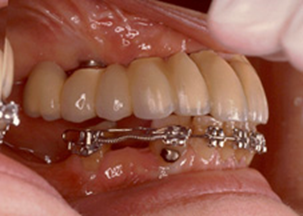

Att ortodontiskt distalföra en tand för att sedan använda tanden som brostöd är ingen vanlig terapi. Oftare väljs en lösning med implantat, en tandstödd extensionsbro eller en partialprotes. Eftersom riskerna är små och prognosen god kan ortodontisk distalisering vara ett utmärkt terapival i specifika fall. Ett exempel kan ses i fig 1.

Fig 1 a-b